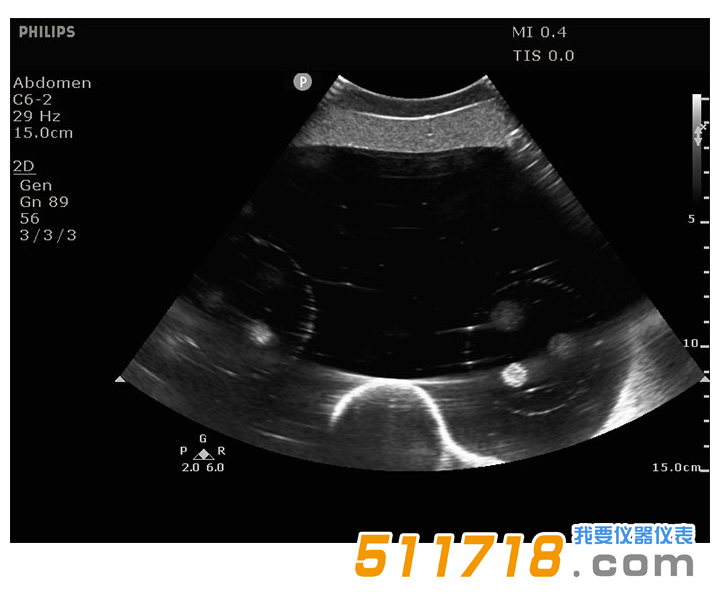

071B超聲圖像

CIRS 071B腹部模體,圖像引導(dǎo)腹部活組織檢查模體包含12個病灶,直徑5-12mm,以三個一組的方式放置在體模內(nèi)的一致位置。它還包括模擬脊柱和肋骨,以及脊柱內(nèi)的“H”標(biāo)記,以幫助確定CT圖像中的頭側(cè)。

在超聲,CT和MRI下可見病變和脊柱。固體聚合物凝膠背景是消聲的,穿刺時不會泄漏。*